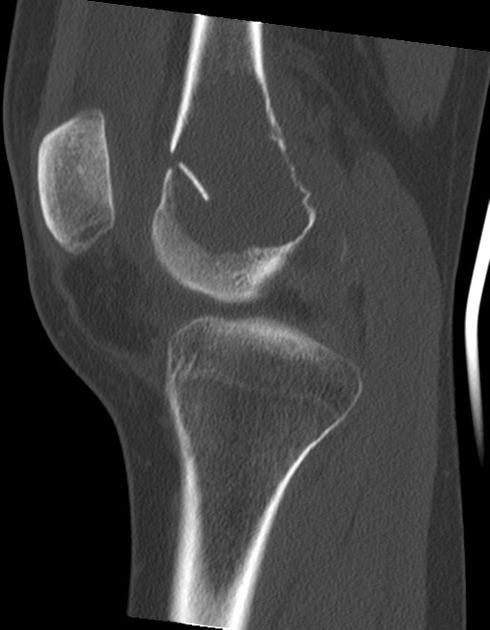

U tế bào khổng lồ

» Thông tin: Nữ giới – 31 tuổi.

» Lâm sàng: Đau khớp gối.